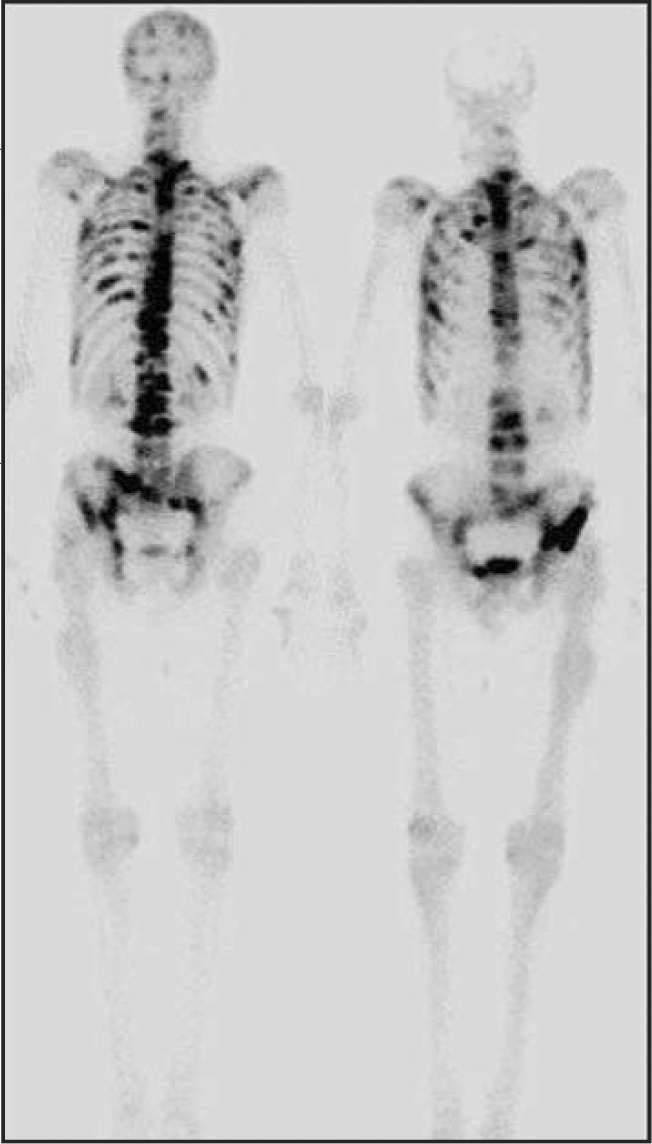

In this total body bone scan using 99mTc linked to methylene diphosphonic acid, the black spots indicate metastases from prostate cancer. The MDP binds to bone and accumulates in areas of cancer.

R. HOWMAN-GILLS, UNIVERSITY OF SYDNEY, AUSTRALIA